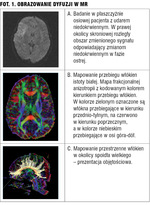

- ocena ostrej fazy udaru, gdyż dyfuzja cząsteczkowa ulega obniżeniu w obszarach niedokrwionych już w ciągu kilkudziesięciu minut od zamknięcia naczynia (fot. 1A),

Najbardziej interesujące jest połączenie map czynnościowych uzyskiwanych w badaniach fMRI (o czym poniżej) i map dyfuzyjnych, gdzie pierwsza z metod umożliwia lokalizację ośrodków korowych, a druga dróg nerwowych w tej okolicy (fot. 1B,C).